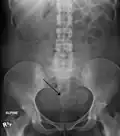

Multiple uterine leiomyoma

Sub-serosal uterine fibroid

Multiple uterine leiomyoma with calcification